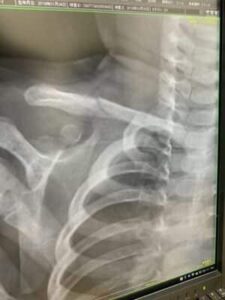

さわやか千葉県民プラザ(鎖骨骨折)